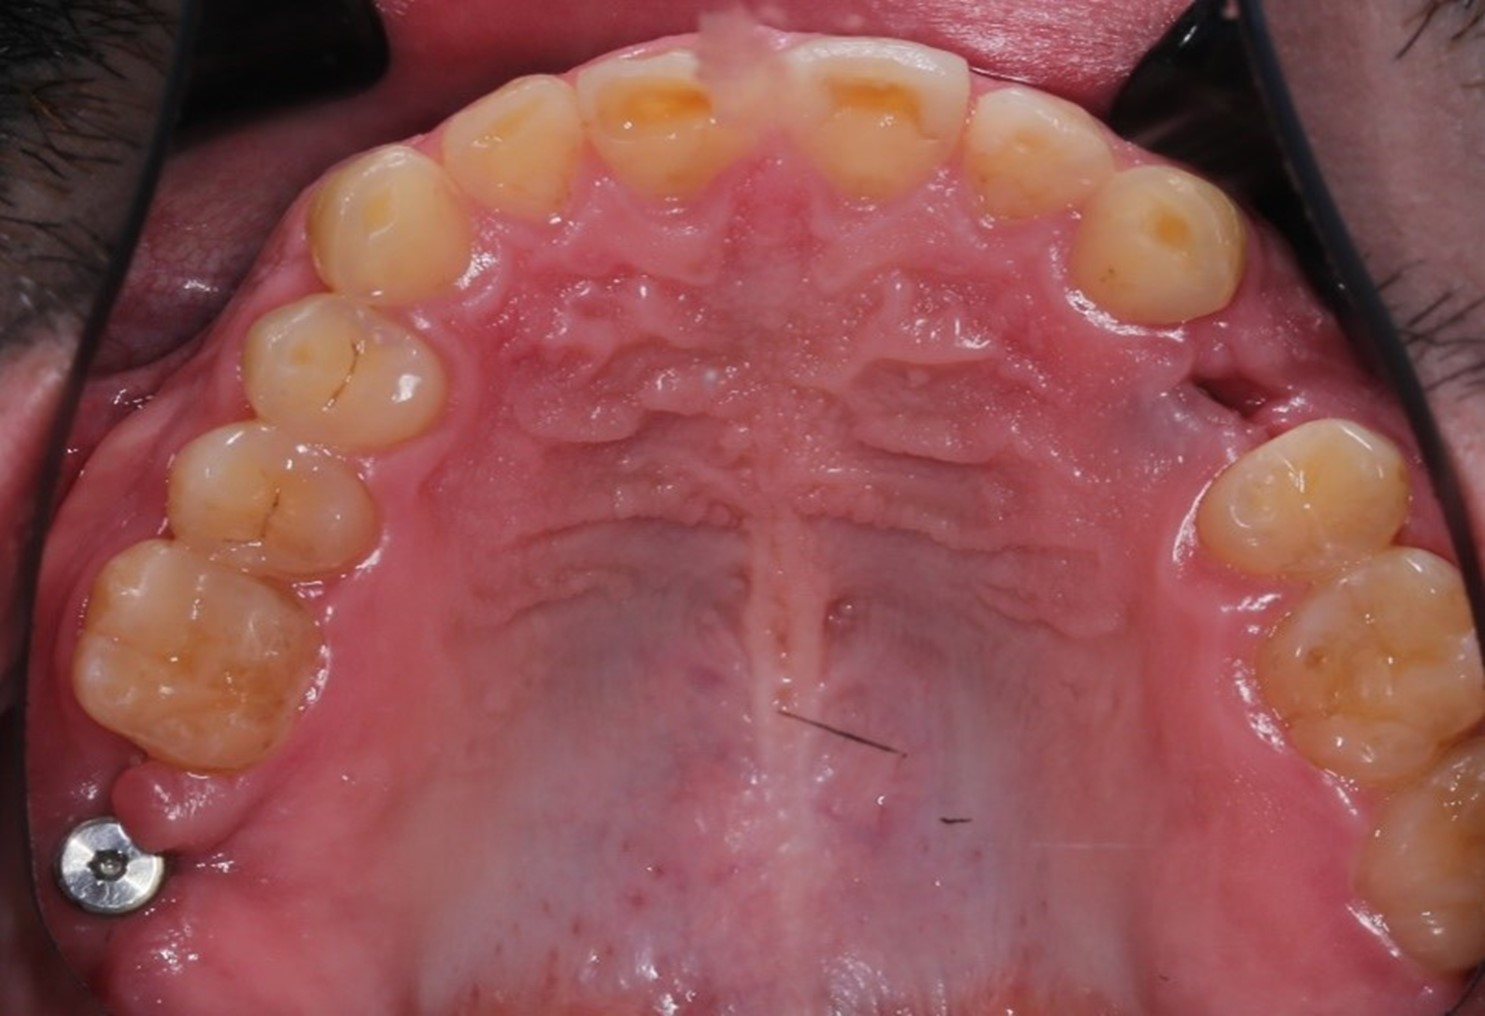

После лечения у терапевта зубы выглядели уже вот так

Но Ваня — кремень: вернулся.

На этой фотографии с временными коронками хорошо видно, какого состояния мы добиваемся на момент перепротезирования. Здоровая десна выглядит именно так. Она умеренно увлажнена, розового цвета, не имеет очагов воспаления. Это как раз результат работы с пародонтологом. Он тонкими кюретами прочищает поддесневые зубные отложения, если они есть, и учит пациента правильным гигиене и уходу.